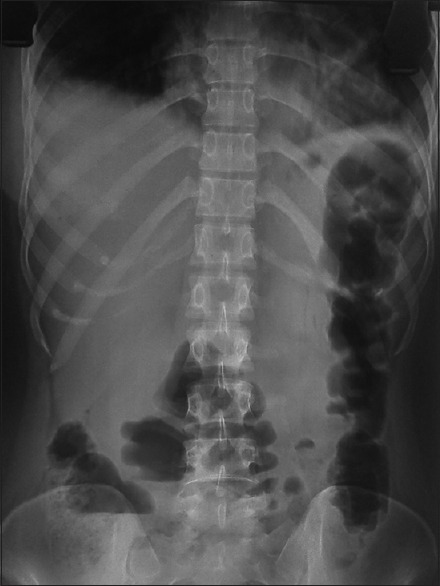

The complete hemogram revealed an increase in total lymphocyte count of 26.5 × 109/L to 62.5 × 109/L from day 12 to day 15 of ATRA therapy. Furthermore, the biochemical parameters revealed an increase in serum lipase, amylase level (peak value 1229 IU/dl and 940 IU/dl, respectively), and mild increase in liver enzymes (serum glutamyl pyruvate transaminase and serum glutamic oxaloacetic transaminase are 346 and 380 IU/dl, respectively). The lipid profile, electrolytes, and calcium level were within normal range (calcium: 9.2 mg/dl, triglyceride: 194 mg/dl) [Figure 1]. The prothrombin time, activated partial thromboplastin time, fibrinogen, and D-dimer were normal. The biochemical parameters were suggestive of AP, and contrast-enhanced computed tomography (CECT) abdomen revealed bulky edematous pancreatitis without any area of necrosis and bilateral pleural effusion [Figures [Figures22 and and33].

| Figure 2:Straight X-ray abdomen in erect posture showing colon cutoff sign